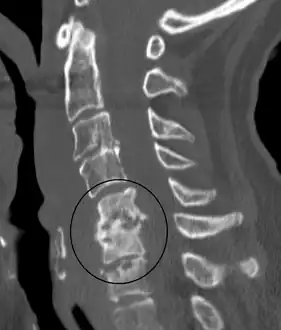

Discitis with anterior abscess (and disc space abscesses) -

An infected disc at the level of C5 C6 causing neurological symptoms